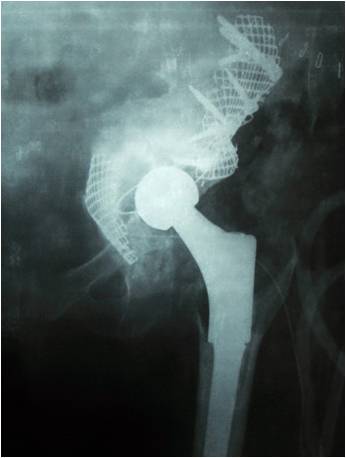

19髋中,18髋的髋臼假体稳定,未发现臼杯在垂直和水平方向大于1mm的移位,也未发现髋臼假体外展角的改变(图1-3)。有1例PaproskyⅢB型患者出现金属网及髋臼杯明显移位等影像学松动表现:术后12月随访时,髋臼上移16.8mm,内移4.7mm;术后28月时,髋臼上移22.7mm,内移5.8mm,髋臼假体外展角较术后减小2.2°(图4-6)。但患者髋关节疼痛不明显,日常生活中能无需手杖独立行走,拒绝再次翻修手术。

辐照异体颗粒骨进行打压植骨髋关节翻修的临床随访已见报道。Buckley等人报道中,经过平均5年随访,153例患者的假体生存率为88%[3]。Hassabala对58例患者进行了48–90月的随访,没有患者因假体松动而需接受再翻修[18]。我们的病例中,仅有1例出现髋臼假体明显移位的影像学松动征象。这例假体松动患者失败的原因更多是由于手术技术因素而非异体骨吸收等原因所致。该患者髋臼底骨质条件极差,在打压植骨过程中发生了臼底骨折,术中未及时发现,导致术后髋臼缺乏足够支撑力,患者负重后髋臼假体及周围植骨床整体出现移位等松动表现。由于异体骨经辐照后较未经辐照的异体骨更硬,因此在打压植骨操作时更易导致髋臼底骨折,因此在后续的手术中,对于髋臼骨质薄弱的患者,我们通常在臼底衬垫金属网以防止骨折发生。

图 4 全髋关节置换术后无菌松动,髋臼PaproskyⅢB型骨缺损

图 5 术后X片见臼底骨折,骨缺损未完全封闭

图 6 术后28月植骨层后连续性放射学透亮线,髋臼假体明显上移松动